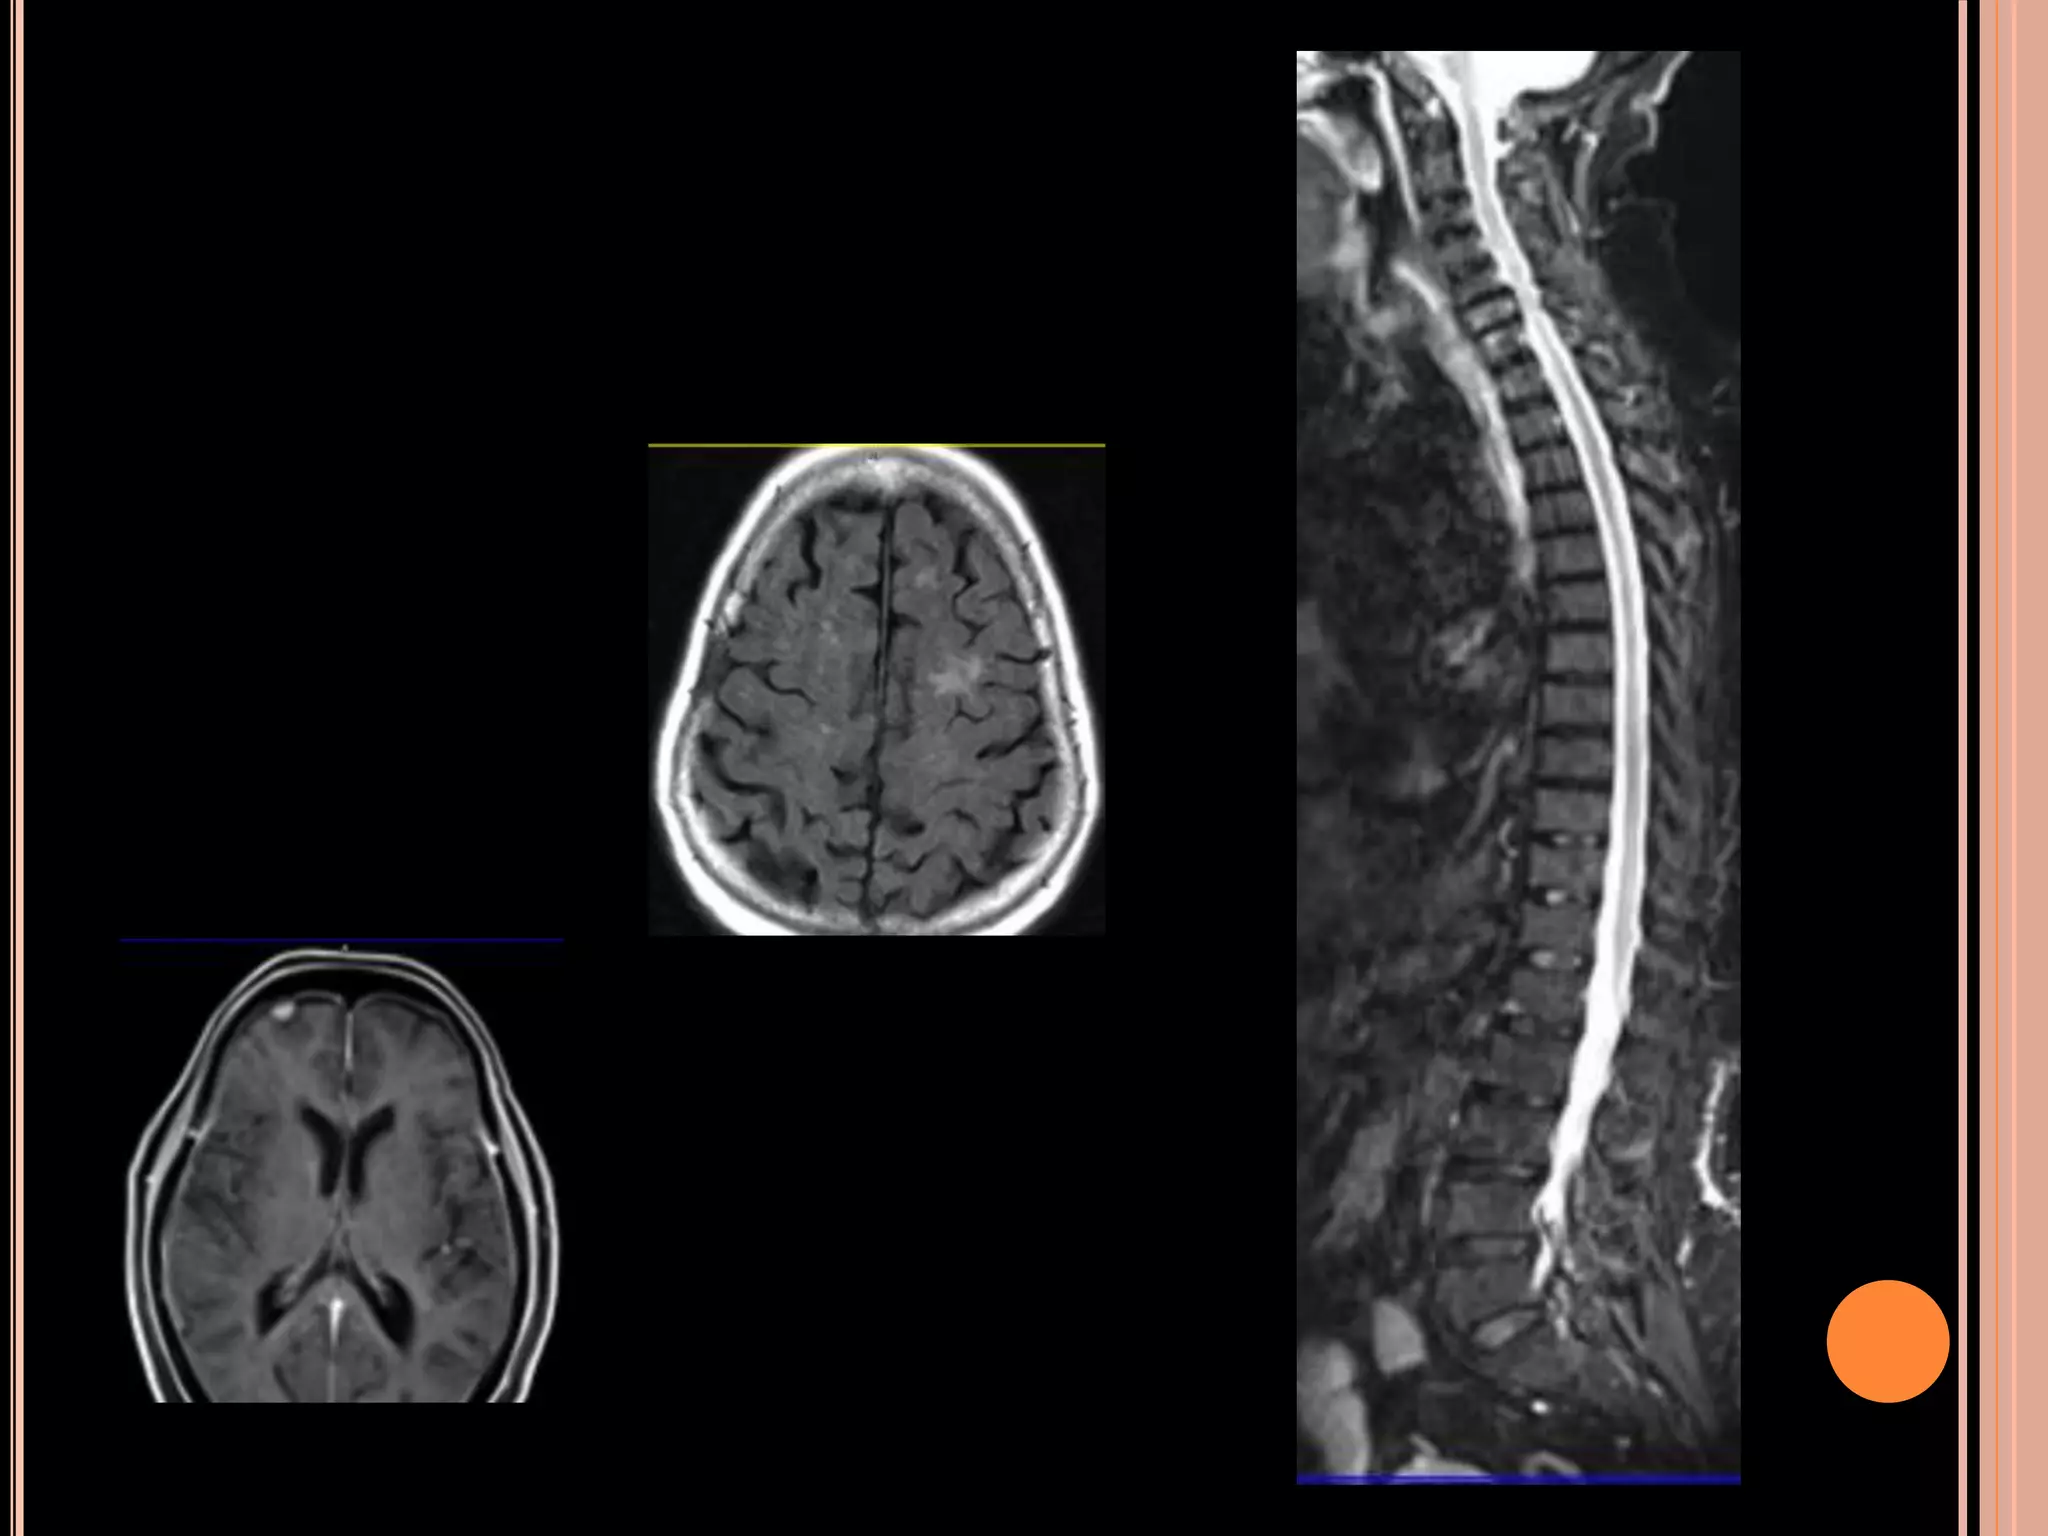

44 year old male, known case of left temporal low grade Glioma

operated upon 6 years back with post-operative RT has now

presented with suspected recurrence.

Simultaneous PET MRI provided information regarding FDG uptake, rCBV, rCBF, Choline/Creatine

and Choline/ NAA ratio from each tissue element at the same time, making a diagnosis of

recurrence accurately that subsequently proved on histology following resurgery.

44 year oldmale, known case of left temporal low grade Glioma operated upon 6 years back with post-operative RT has now presented with suspected recurrence. Simultaneous PET MRI provided information regarding FDG uptake, rCBV, rCBF, Choline/Creatine and Choline/ NAA ratio from each tissue element at the same time, making a diagnosis of recurrence accurately that subsequently proved on histology following resurgery.